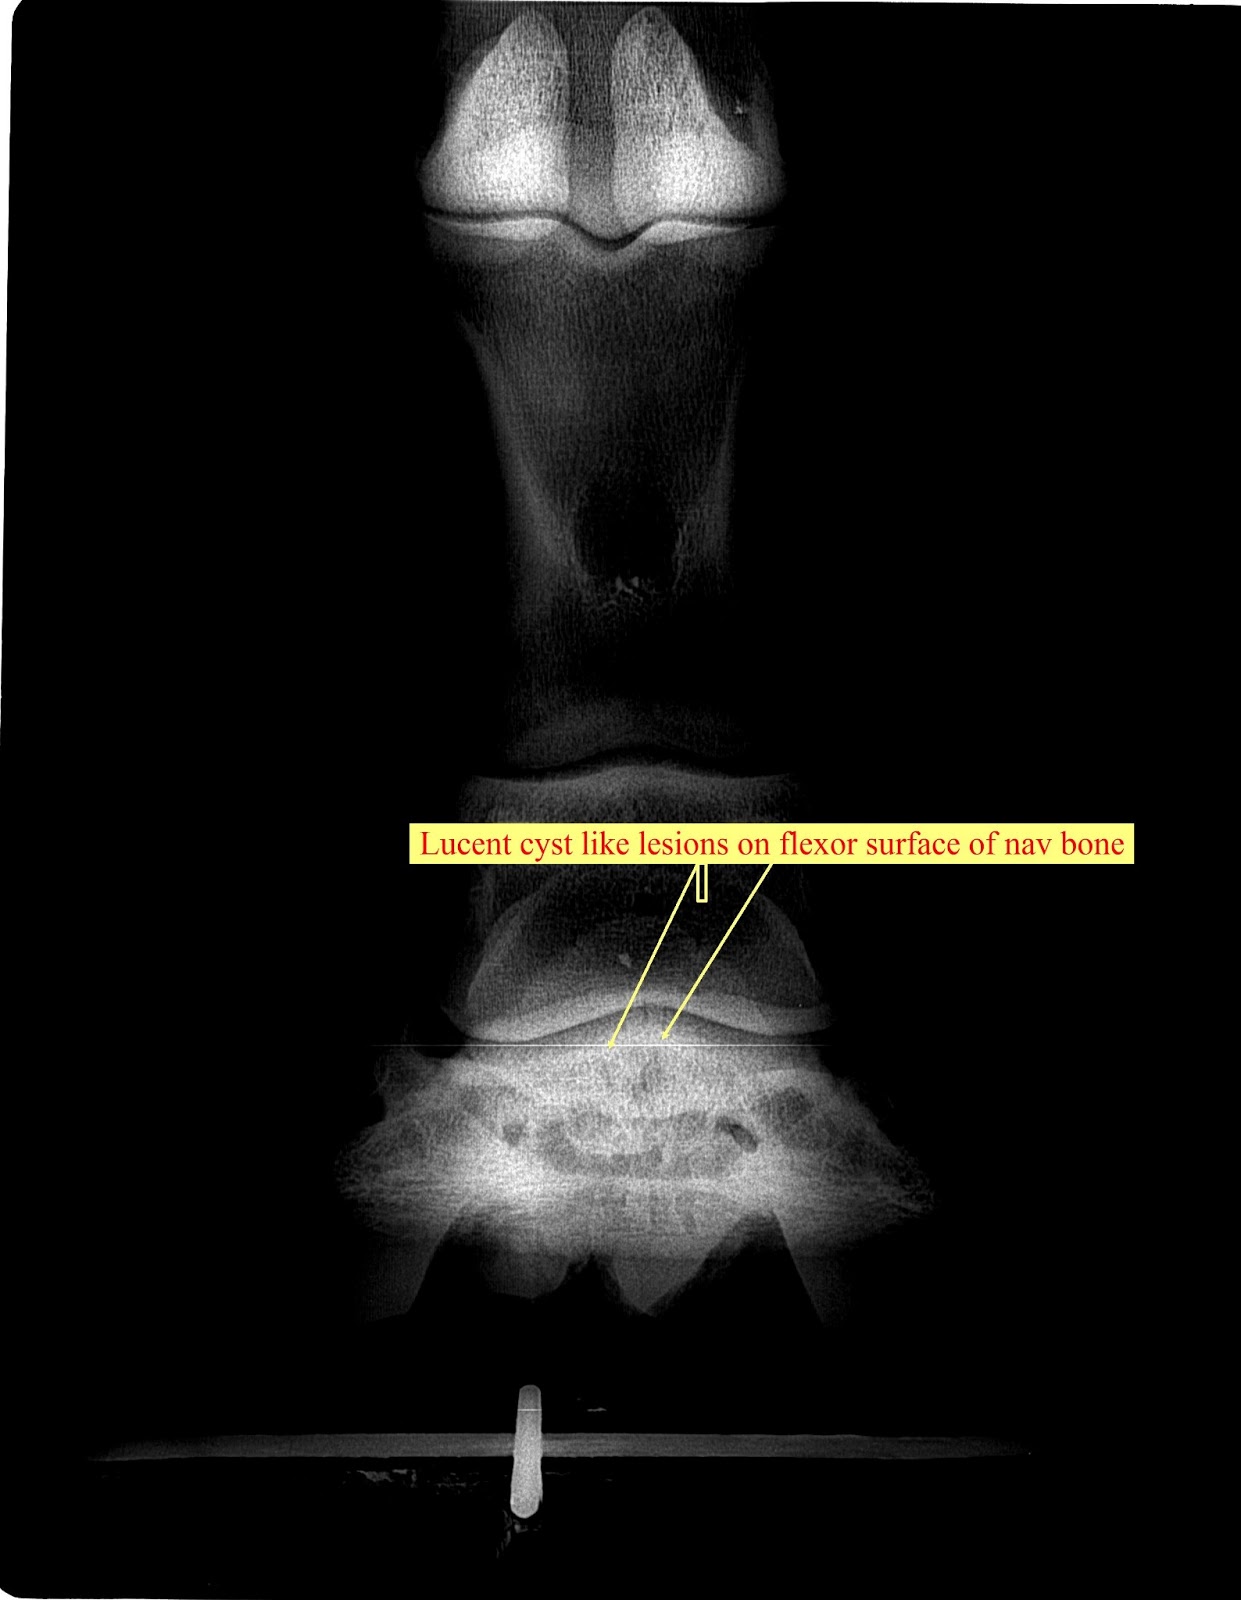

From swiftsureequine.com

December Navicular Cyst Swiftsure Equine Equine Navicular Bursa Injections The significance of a positive response to analgesia of the navicular bursa has not been established. Following diagnostic imaging, injection of the navicular bursa may be indicated. Needle placement for treatment of the navicular. Injection of the navicular bursa is commonly performed from the palmar aspect of the limb, which results in penetration of the deep digital flexor tendon (ddft).. Equine Navicular Bursa Injections.